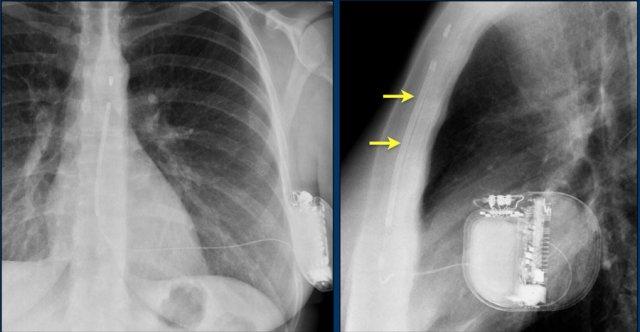

Đây là hình ảnh máy tạo nhịp hai thất với ba điện cực.

Điện cực tạo nhịp nhĩ phải nằm ở tiểu nhĩ phải.

Điện cực này đi xuống dưới vào nhĩ phải trước, sau đó vòng lên trên và ra trước, nơi nó được neo chặt vào các bè cơ của tiểu nhĩ.

Điện cực thất trái đi qua nhĩ phải và xoang vành, cuối cùng được đặt ở phía sau vào một tĩnh mạch tim bên trái.

Các phát hiện bao gồm:

- Hai điện cực thượng tâm mạc kết nối với máy tạo nhịp

- ICD

- Hai điện cực đến mỏm thất phải

- Một điện cực chứa hai cuộn sốc điện

- Van ba lá (mũi tên)

- Van hai lá